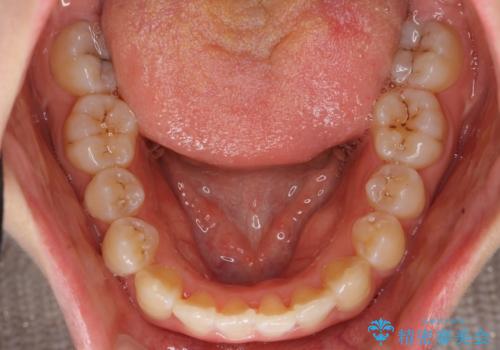

上下の前歯のがたつき 歯を抜かずに矯正

- 上下の前歯のがたつきを主訴に来院。

歯を抜かずに前歯を揃えています。

奥歯を後ろに下げたりなどはしていません。

奥歯を外に広げ、前歯中心に歯を少し削っていますが、健康には問題ない範囲で行なっています。